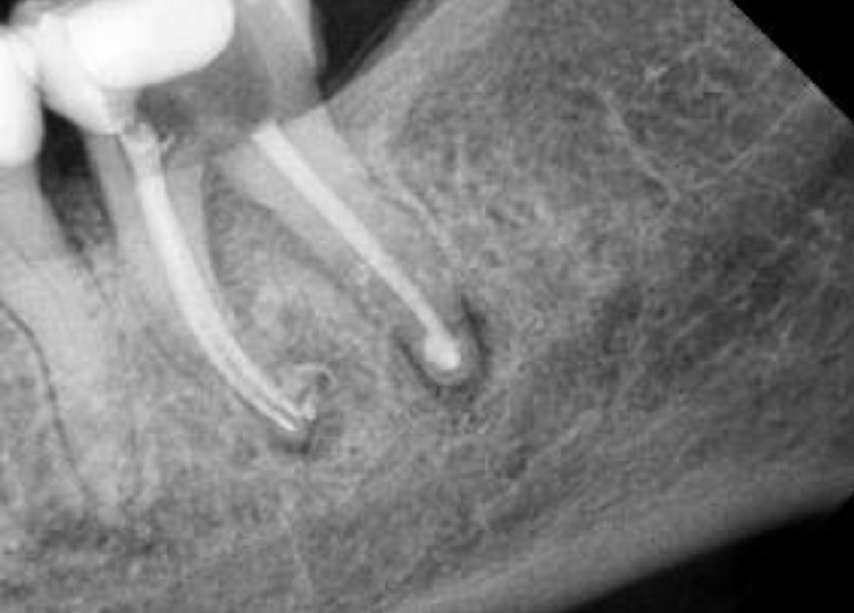

Wenn man sich dieses präoperative Röntgenbild ansieht, sind zwei Hinweise zu diesem endodontischen Fall zu erkennen (Abb. 1): Obliteration der Pulpakammer und enge Kanäle Ungewöhnliche Anatomie der distalen Wurzel

Mit hochtourigen Diamantbohrern wurde eine konventionelle Zugangskavität angelegt und die drei Öffnungen wurden mit Ultraschallspitzen lokalisiert. Die KFeile #08 wurde verwendet, um das endodontische System aller Wurzeln zu erkunden, wobei aber der Apex im distalen Kanal nicht erreicht werden konnte. Das Aufweiten und die Instrumentierung im mittleren Drittel erfolgten mit einer reziprok arbeitenden kleinen (gelben) EdgeOne-Feile (Edge Endo, Albuquerque, NM), die mit Einwärts-Auswärts-Bewegungen von 1-2 mm im Wechsel mit bürstenden Bewegungen zum koronalen Erweitern der Kanäle verwendet wurde. Es wurde eine regelmäßige und reichliche manuelle Spülung mit Lösungen von 5% Natriumhypochlorit durchgeführt. Nach der Aufbereitung des koronalen und mittleren Teils wurde die Arbeitslänge mit der K-Feile #10 bestimmt und das Aufbereitungsverfahren mit martensitischen X7-Instrumenten (Edge Endo, Albuquerque, NM) in den Größen 17 und 25, Konizität .04 abgeschlossen. Die Instrumente wurden mit reziproker Rotation im Uhrzeigersinn (150°-30°) verwendet, um die Torsions- und Biegebelastung zu verringern (Abb. 2).

FALLBERICHT: Abb.1 Abb.2

Die abschließende Spülung erfolgte zunächst eine Minute mit schallaktivierter EDTA-Lösung, gefolgt von einer Minute mit schallaktivierter NaOCl-Lösung. Das Wurzelkanalsystem wurde gespült, getrocknet und dann mit einer hydraulischen Single-Cone-Technik und einem biokeramischen Sealer (BUSA, BC Sealer) verschlossen. Zur Überprüfung der Behandlungsqualität wurden zwei periapikale Röntgenaufnahmen aus verschiedenen Winkeln angefertigt (Abb. 3-4).

Der Verdacht des Klinikers auf eine ungewöhnliche Anatomie der distalen Wurzel wurde durch das abgewinkelte Röntgenbild bestätigt, das eine abrupte versteckte Krümmung im apikalen Drittel des Kanals zeigte. Trotzdem ermöglichte der Crown-Down-Ansatz (zunächst Aufbereitung des koronalen und mittleren Teils, wodurch koronale Interferenzen reduziert werden) und die richtige Auswahl sehr flexibler und widerstandsfähiger

Abb.3 Abb.4